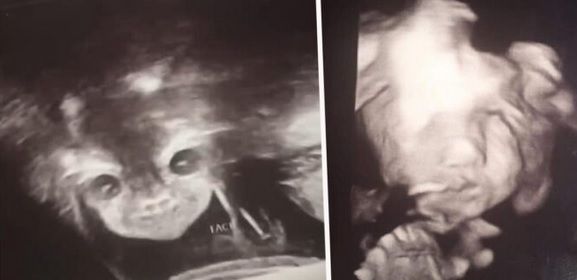

8 nov. 2019, 12:12ActualLa ecografie, a urmat șocul: "E copilul diavolului! Mi se uită direct în suflet!" Ce purta în pântec